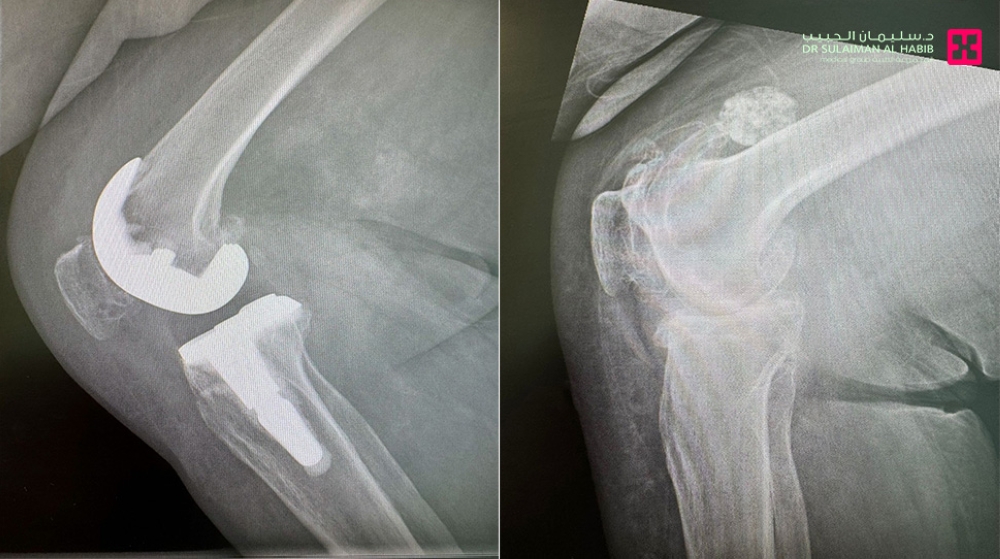

خلال العملية، التي استغرقت نحو ساعتين ونصف، استخدم الفريق الطبي تقنية الروبوت الجراحي المتطورة، حيث تم تزويد النظام الروبوتي بكافة البيانات الخاصة بالمراجعة، بما في ذلك قياسات الركبة، وطبيعة العظام، وحالة الأنسجة المحيطة بالمفصل.

يقوم الروبوت الجراحي برفع القياسات بدقة متناهية، وتحديد مواضع القطع الجراحي وزواياه، واختيار المفصل الصناعي الأنسب لحالة المريض، بما يضمن أعلى مستويات التوافق بين المفصل الصناعي وبنية الركبة الطبيعية. هذه الدقة تقلل من هامش الخطأ البشري إلى أدنى مستوى، وتضمن توزيعًا مثاليًا للحركة والضغط داخل المفصل بعد الزراعة.

كما تم خلال العملية تصحيح الانحراف والتقوس في الركبة باستخدام دعامة متطورة تشمل الساق والفخذ، ما أسهم في استعادة المحور الطبيعي للطرف السفلي وتحقيق توازن أفضل أثناء المشي.